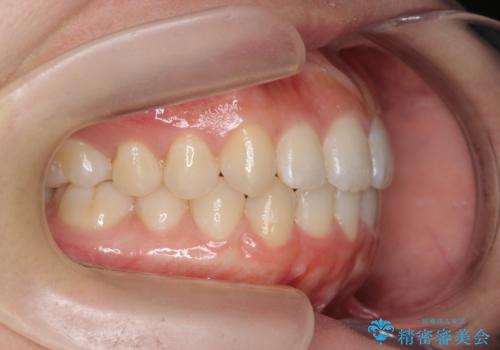

前歯のすれ違い インビザラインで行うマウスピース矯正

- 前歯のガタつき、でこぼこ、前後が逆になっている噛み合わせの改善を求めて来院されました。

治療の装置が目立たず歯ブラシのしやすいマウスピース矯正インビザラインでの治療を計画します。

20時間/日の装用時間をしっかりと守っていただき、きれいな歯並びを手に入れることができました。